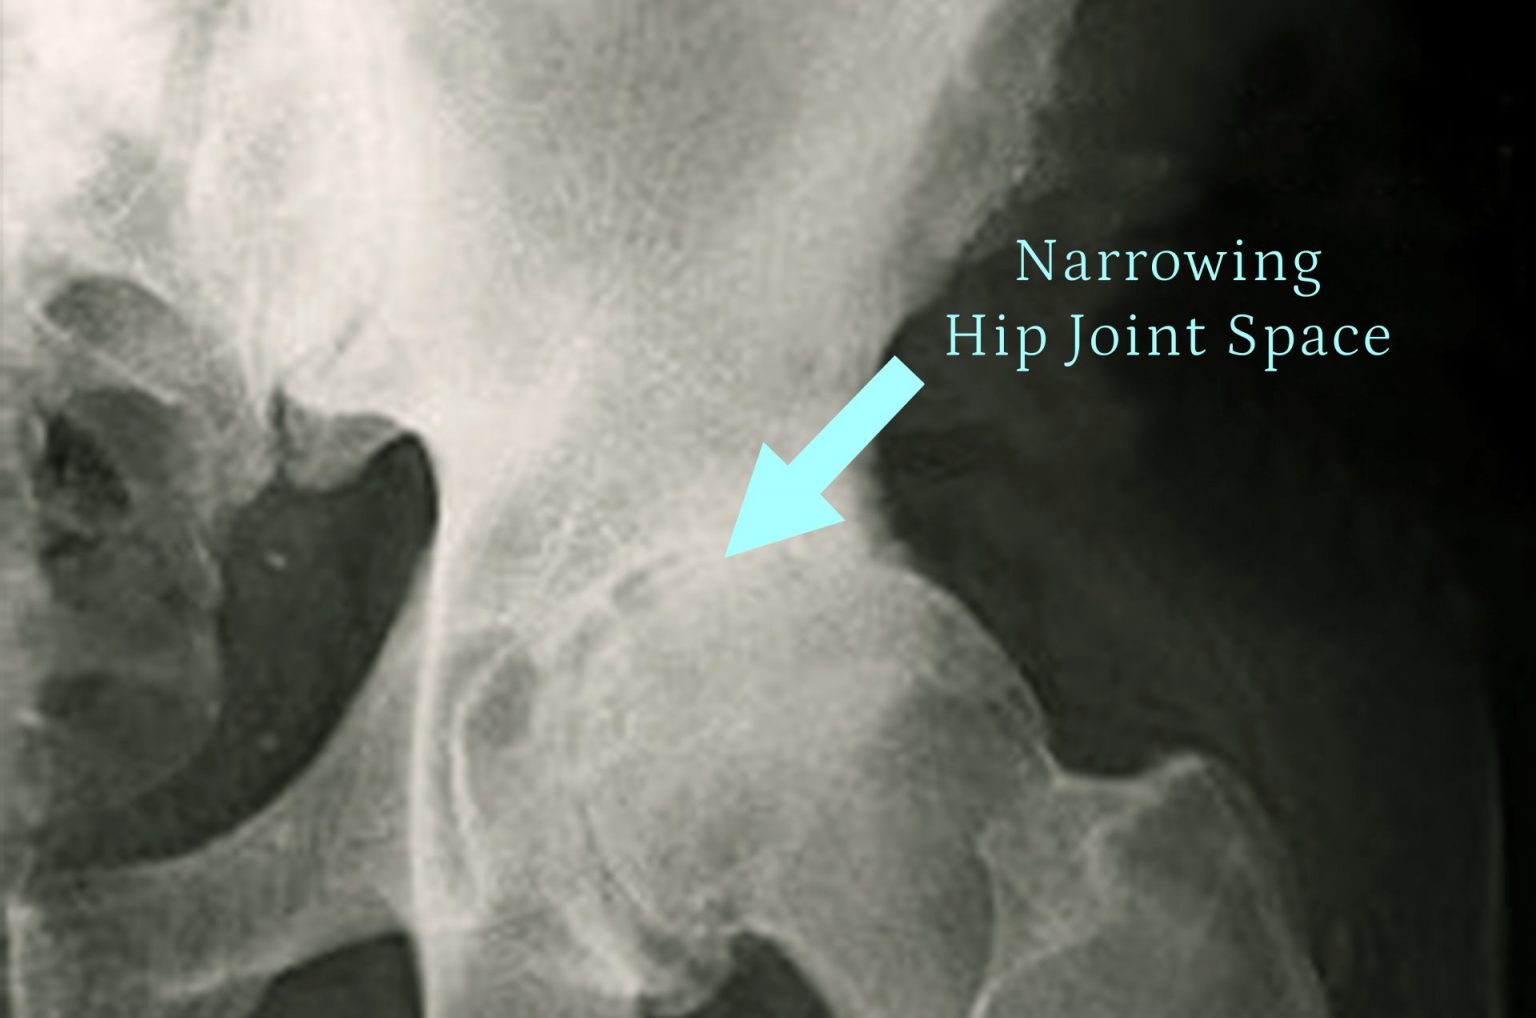

• X-rays: Do your X-rays show severe hip damage, such as arthritis or a fracture?

X-rays

X-rays are an important part of the diagnostic process for hip pain. X-rays can show damage to the hip joint, such as arthritis or a fracture. This information can help your doctor determine if you are a candidate for hip replacement surgery.

• Facet 1: Arthritis

Arthritis is a common cause of hip pain. X-rays can show the extent of arthritis damage to the hip joint. Severe arthritis damage may warrant hip replacement surgery.

• Facet 2: Fracture

A hip fracture can also cause severe hip pain. X-rays can show the location and severity of the fracture. A severe hip fracture may require surgery, including hip replacement surgery.

• Facet 3: Other damage

X-rays can also show other damage to the hip joint, such as a torn ligament or a dislocated hip. This information can help your doctor determine the best course of treatment.

If you are experiencing hip pain, it is important to see your doctor for an evaluation. X-rays are an important part of the diagnostic process, and they can help your doctor determine if you are a candidate for hip replacement surgery.